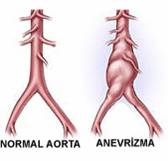

Anevrizma damarların kalıcı olarak genişlemesi veya balonlaşmasıdır. Anevrizma en sık vücudun en büyük atardamarı olan aortada gelişir. Anevrizma zamanla daha da genişler ve tedavi edilmediği takdirde patlar ve çoğunlukla ölüme neden olur. Çoğu kez anevrizmalar bir şikayete neden olmaz ve tesadüfen başka nedenlerle yapılan incelemelerde fark edilir Anevrizma erkenden teşhis edildiğinde kalıcı tedavisi mümkündür. Anevrizmanın klasik tedavisi ameliyat ile genişlemiş damar bölümünün suni bir damar ile değiştirilmesidir. Daha az rahatsızlık verebilecek bir başka tedavi yöntemi ise özel bazı kateterler ile damarın içine girilip, anevrizmanın olduğu damar bölümüne içerden suni damarın yerleştirilmesidir.

Anevrizma damarların kalıcı olarak genişlemesi veya balonlaşmasıdır. Anevrizma en sık vücudun en büyük atardamarı olan aortada gelişir. Anevrizma zamanla daha da genişler ve tedavi edilmediği takdirde patlar ve çoğunlukla ölüme neden olur. Çoğu kez anevrizmalar bir şikayete neden olmaz ve tesadüfen başka nedenlerle yapılan incelemelerde fark edilir Anevrizma erkenden teşhis edildiğinde kalıcı tedavisi mümkündür. Anevrizmanın klasik tedavisi ameliyat ile genişlemiş damar bölümünün suni bir damar ile değiştirilmesidir. Daha az rahatsızlık verebilecek bir başka tedavi yöntemi ise özel bazı kateterler ile damarın içine girilip, anevrizmanın olduğu damar bölümüne içerden suni damarın yerleştirilmesidir.

Anevrizma damarların kalıcı olarak genişlemesi veya balonlaşmasıdır. Anevrizma en sık vücudun en büyük atardamarı olan aortada gelişir. Anevrizma zamanla daha da genişler ve tedavi edilmediği takdirde patlar ve çoğunlukla ölüme neden olur. Anevrizmadan ölüm toplumda ölüm nedenleri arasında 13. sıradadır.